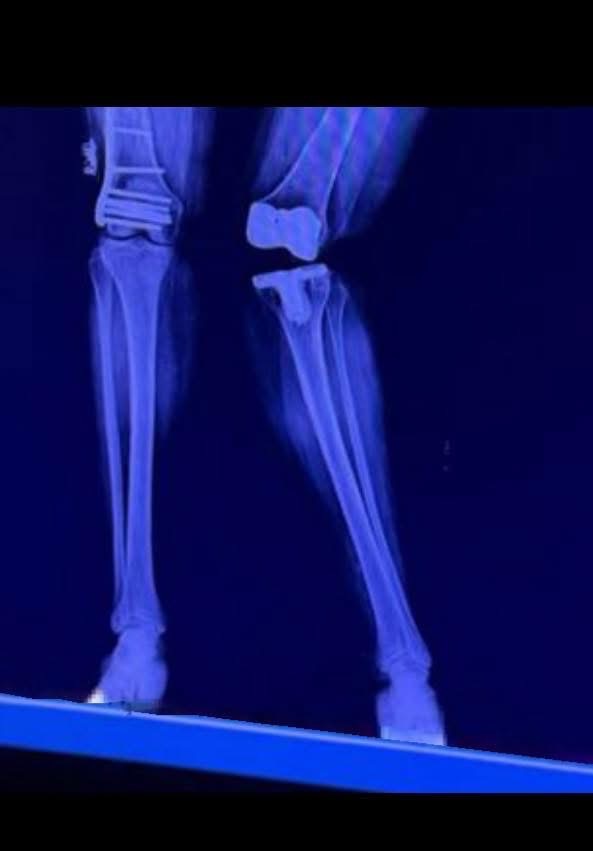

My name is “Suzy” Britz, I’ve spent my life helping others heal, rescuing animals, and as a Texas Realtor, guiding families and investors to build wealth. Now, I find myself on the other side, in urgent need of support. After a sudden fracture on August 13th left my tibia broken in half, I’ve been unable to walk or work. This injury, along with past orthopedic conditions and a misaligned knee replacement, has left me facing multiple surgeries and months of rehabilitation.

My savings are gone, and emergency SSDI does not cover my rent, medical care, or the accessibility modifications I need to recover safely. I urgently need help with housing, utilities, medical co-pays, physical therapy, transportation, and accessibility equipment. I am currently in therapy twice a week to gain enough strength for two critical surgeries: a total left knee replacement and a revision to a hinged knee replacement.